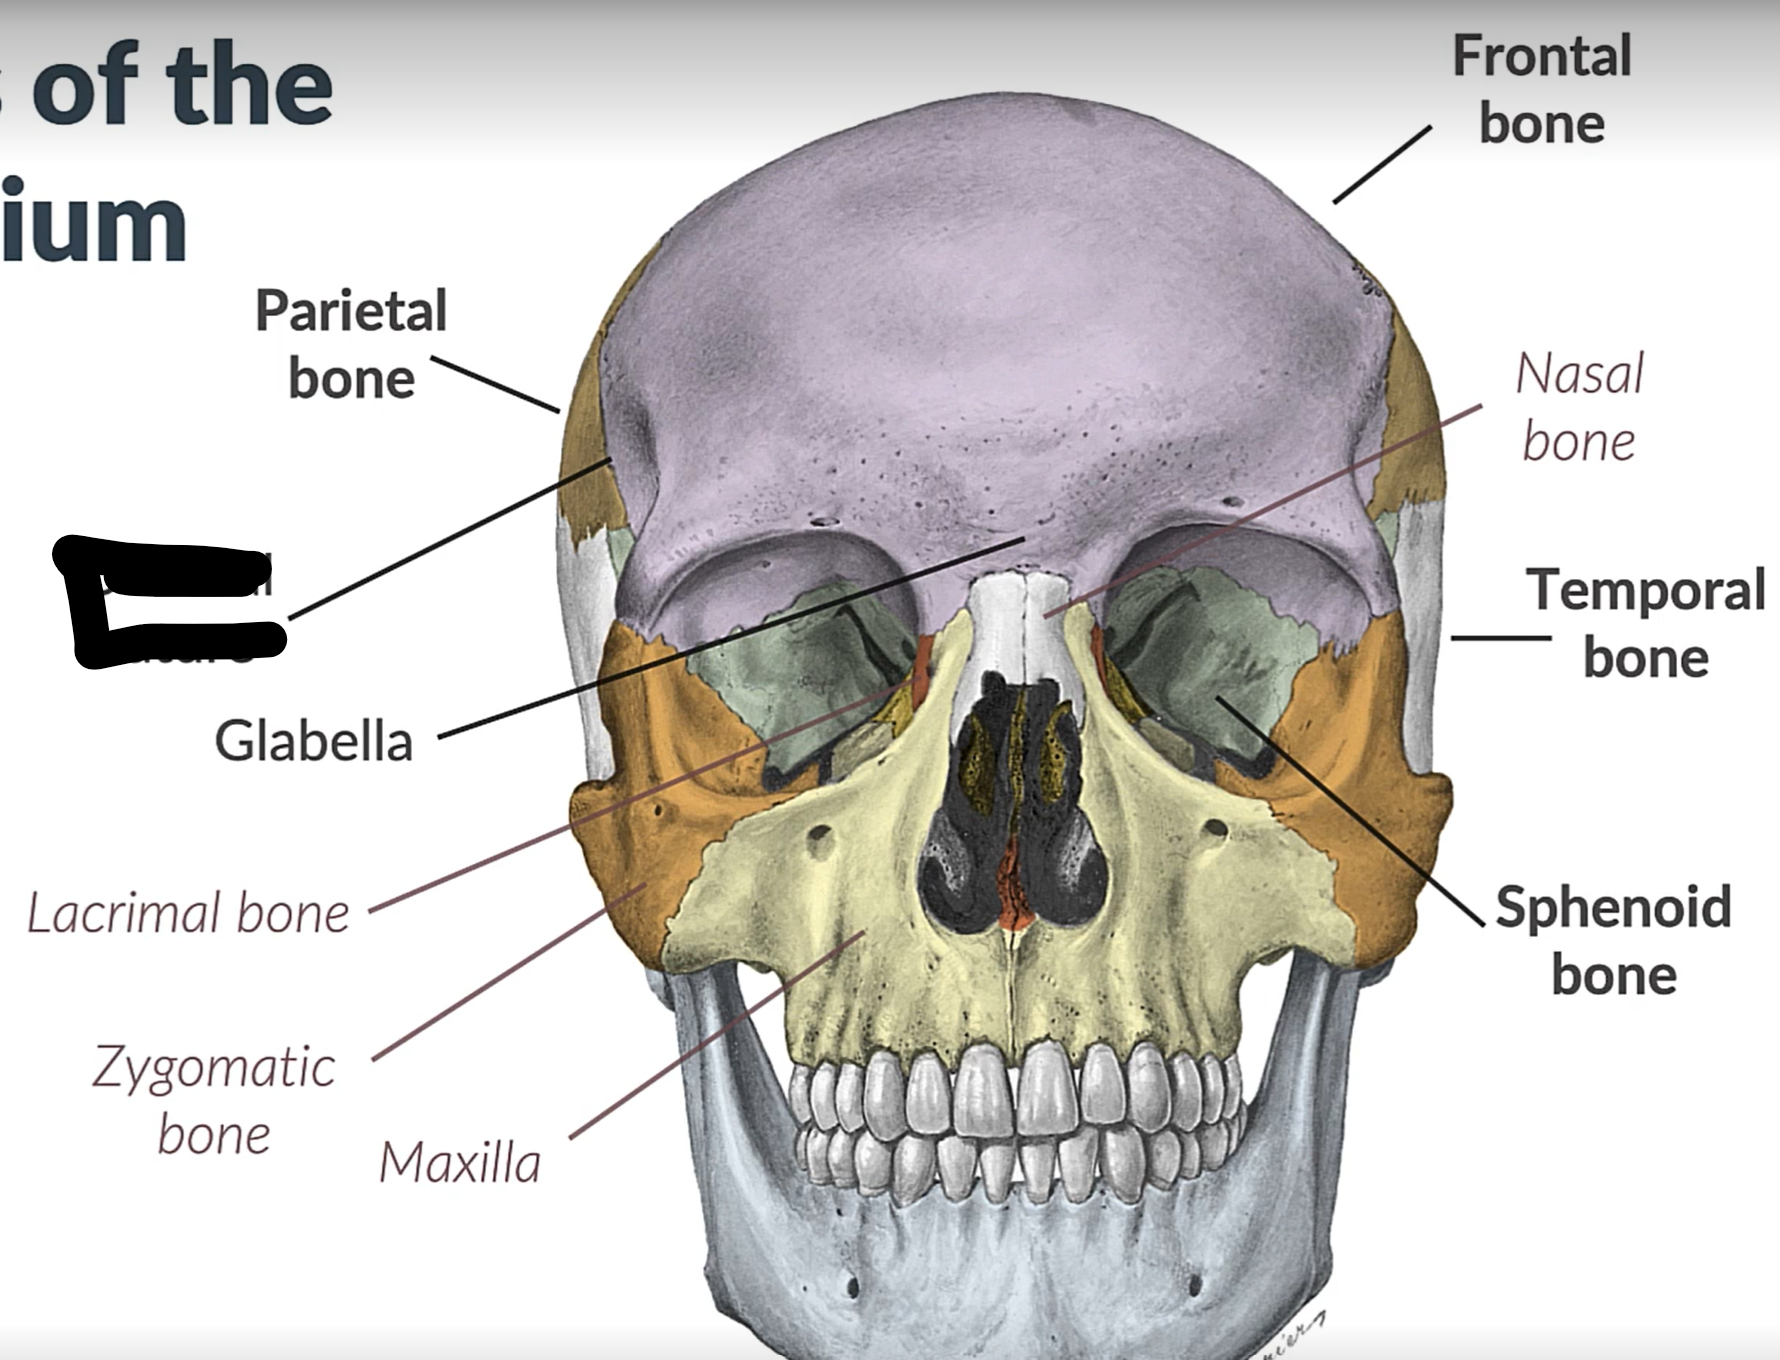

Parietal bone

Frontal bone

Temporal bone

Sphenoid bone

Zygomatic bone

Lacrimal bone

Coronal suture

Maxilla